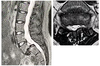

# Espondilolisteses - Na avaliação radiológica, qual a utilidade da ressonância magnética?

- Avaliação dos elementos neurais - **Bulging** do disco → pseudohérnia - Avalia a degeneração discal